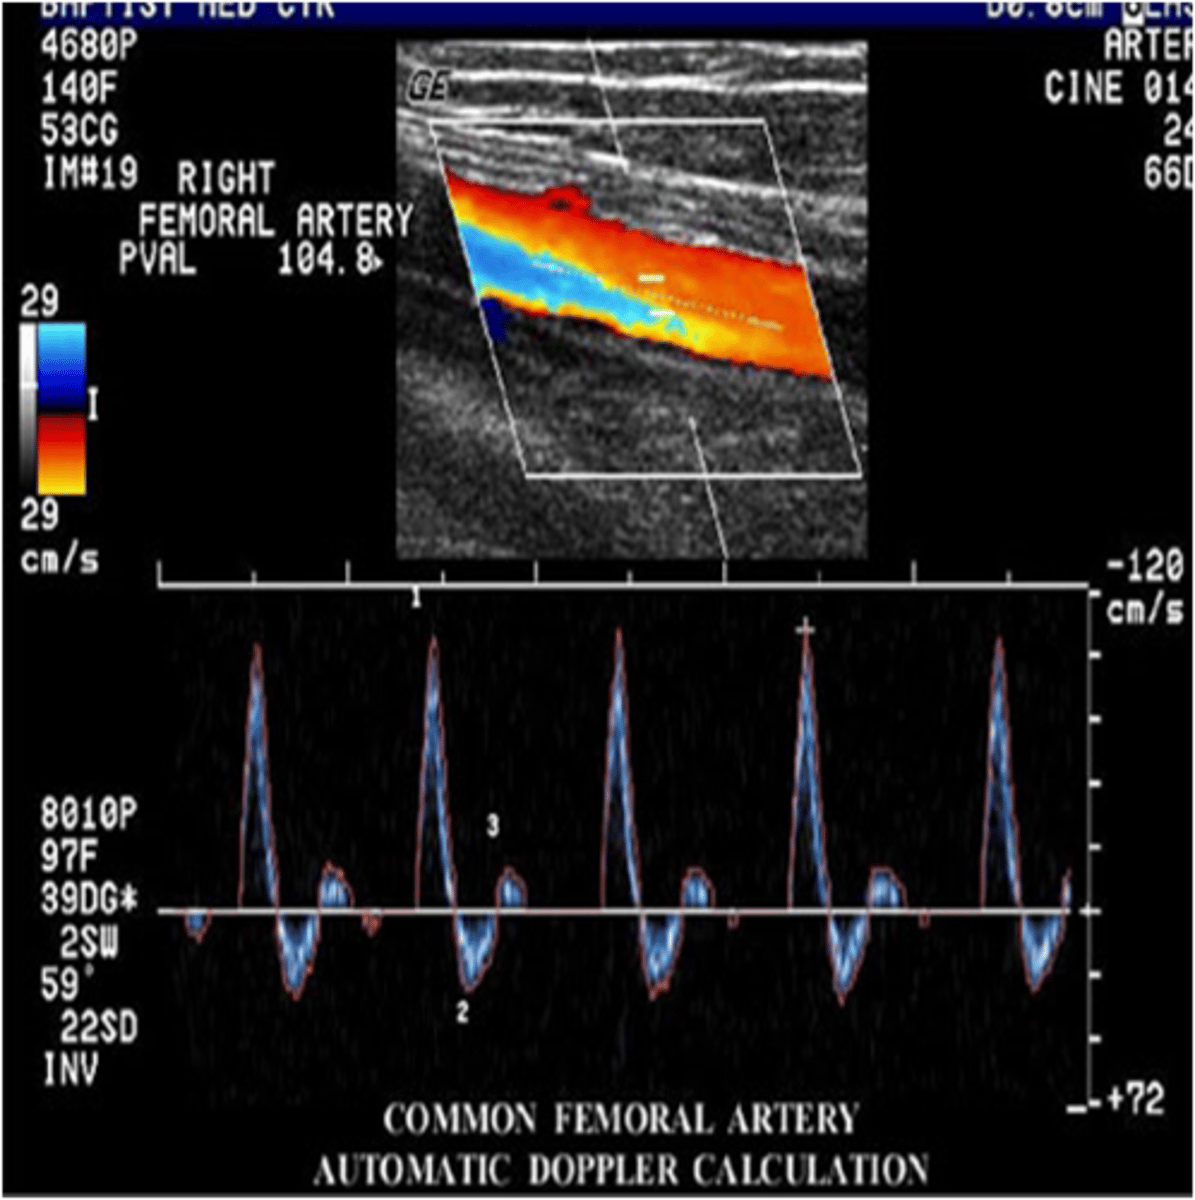

Unlike the cerebrovascular system that feeds the brain and requires continuous blood flow even during diastole when the heart is relaxing, the peripheral vascular system that feeds blood to the upper extremities (arms) and lower extremities (legs)has a very different waveform pattern. The term that best describes the normal waveform pattern associated with the peripheral arterial system of the legs is...

uniphasic

biphasic

triphasic

quadriphasic

The appearance of the spectral Doppler waveform and the velocity recorded in this image represents...

no stenosis

mild stenosis

significant stenosis

total occlusion